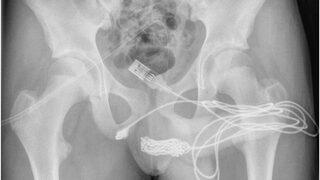

Cinsel organından çıktı: Tam 5 metre! Doktorlar şaşkınlığını gizleyemedi

05-09-2022 11:17

İngiltere’de yaşayan ve ismi açıklanmayan 15 yaşındaki bir erkek çocuk cinsel organının boyunu ölçmek için penisine USB kablosu yerleştirdi. Ancak USB kablosunu penisinden çıkaramaması ve idrarında kan görülmesi üzerine annesi tarafından hastaneye kaldırıldı. Doktorlar yabancı cismi ameliyatla çıkartmayı başardı.

Devamını Oku